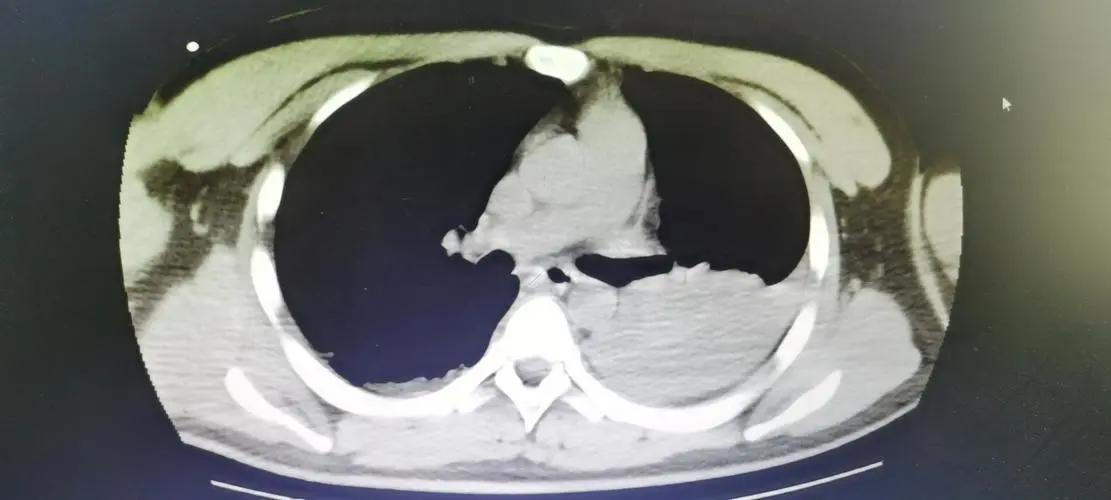

再综合选择辅助检查,必要时结合CT以及三维重建技术,同时,根据患者情况选择MRI、血管造影等来判断患者基本情况。

避免漏诊,对患者进行X线检查的同时完善CT检查,其可以显示出骶骨骨折和后环的移位不明显的骨折,还可以反映出骶骨的骨密度。

之后再行MRI检查,对67例患者进行研究发现CT检查诊断骶骨骨折的确诊率为74.6%,MRI的正确诊断率为100%。 使用MRI在骨盆前环骨折的患者中发现了骨盆后环损伤。